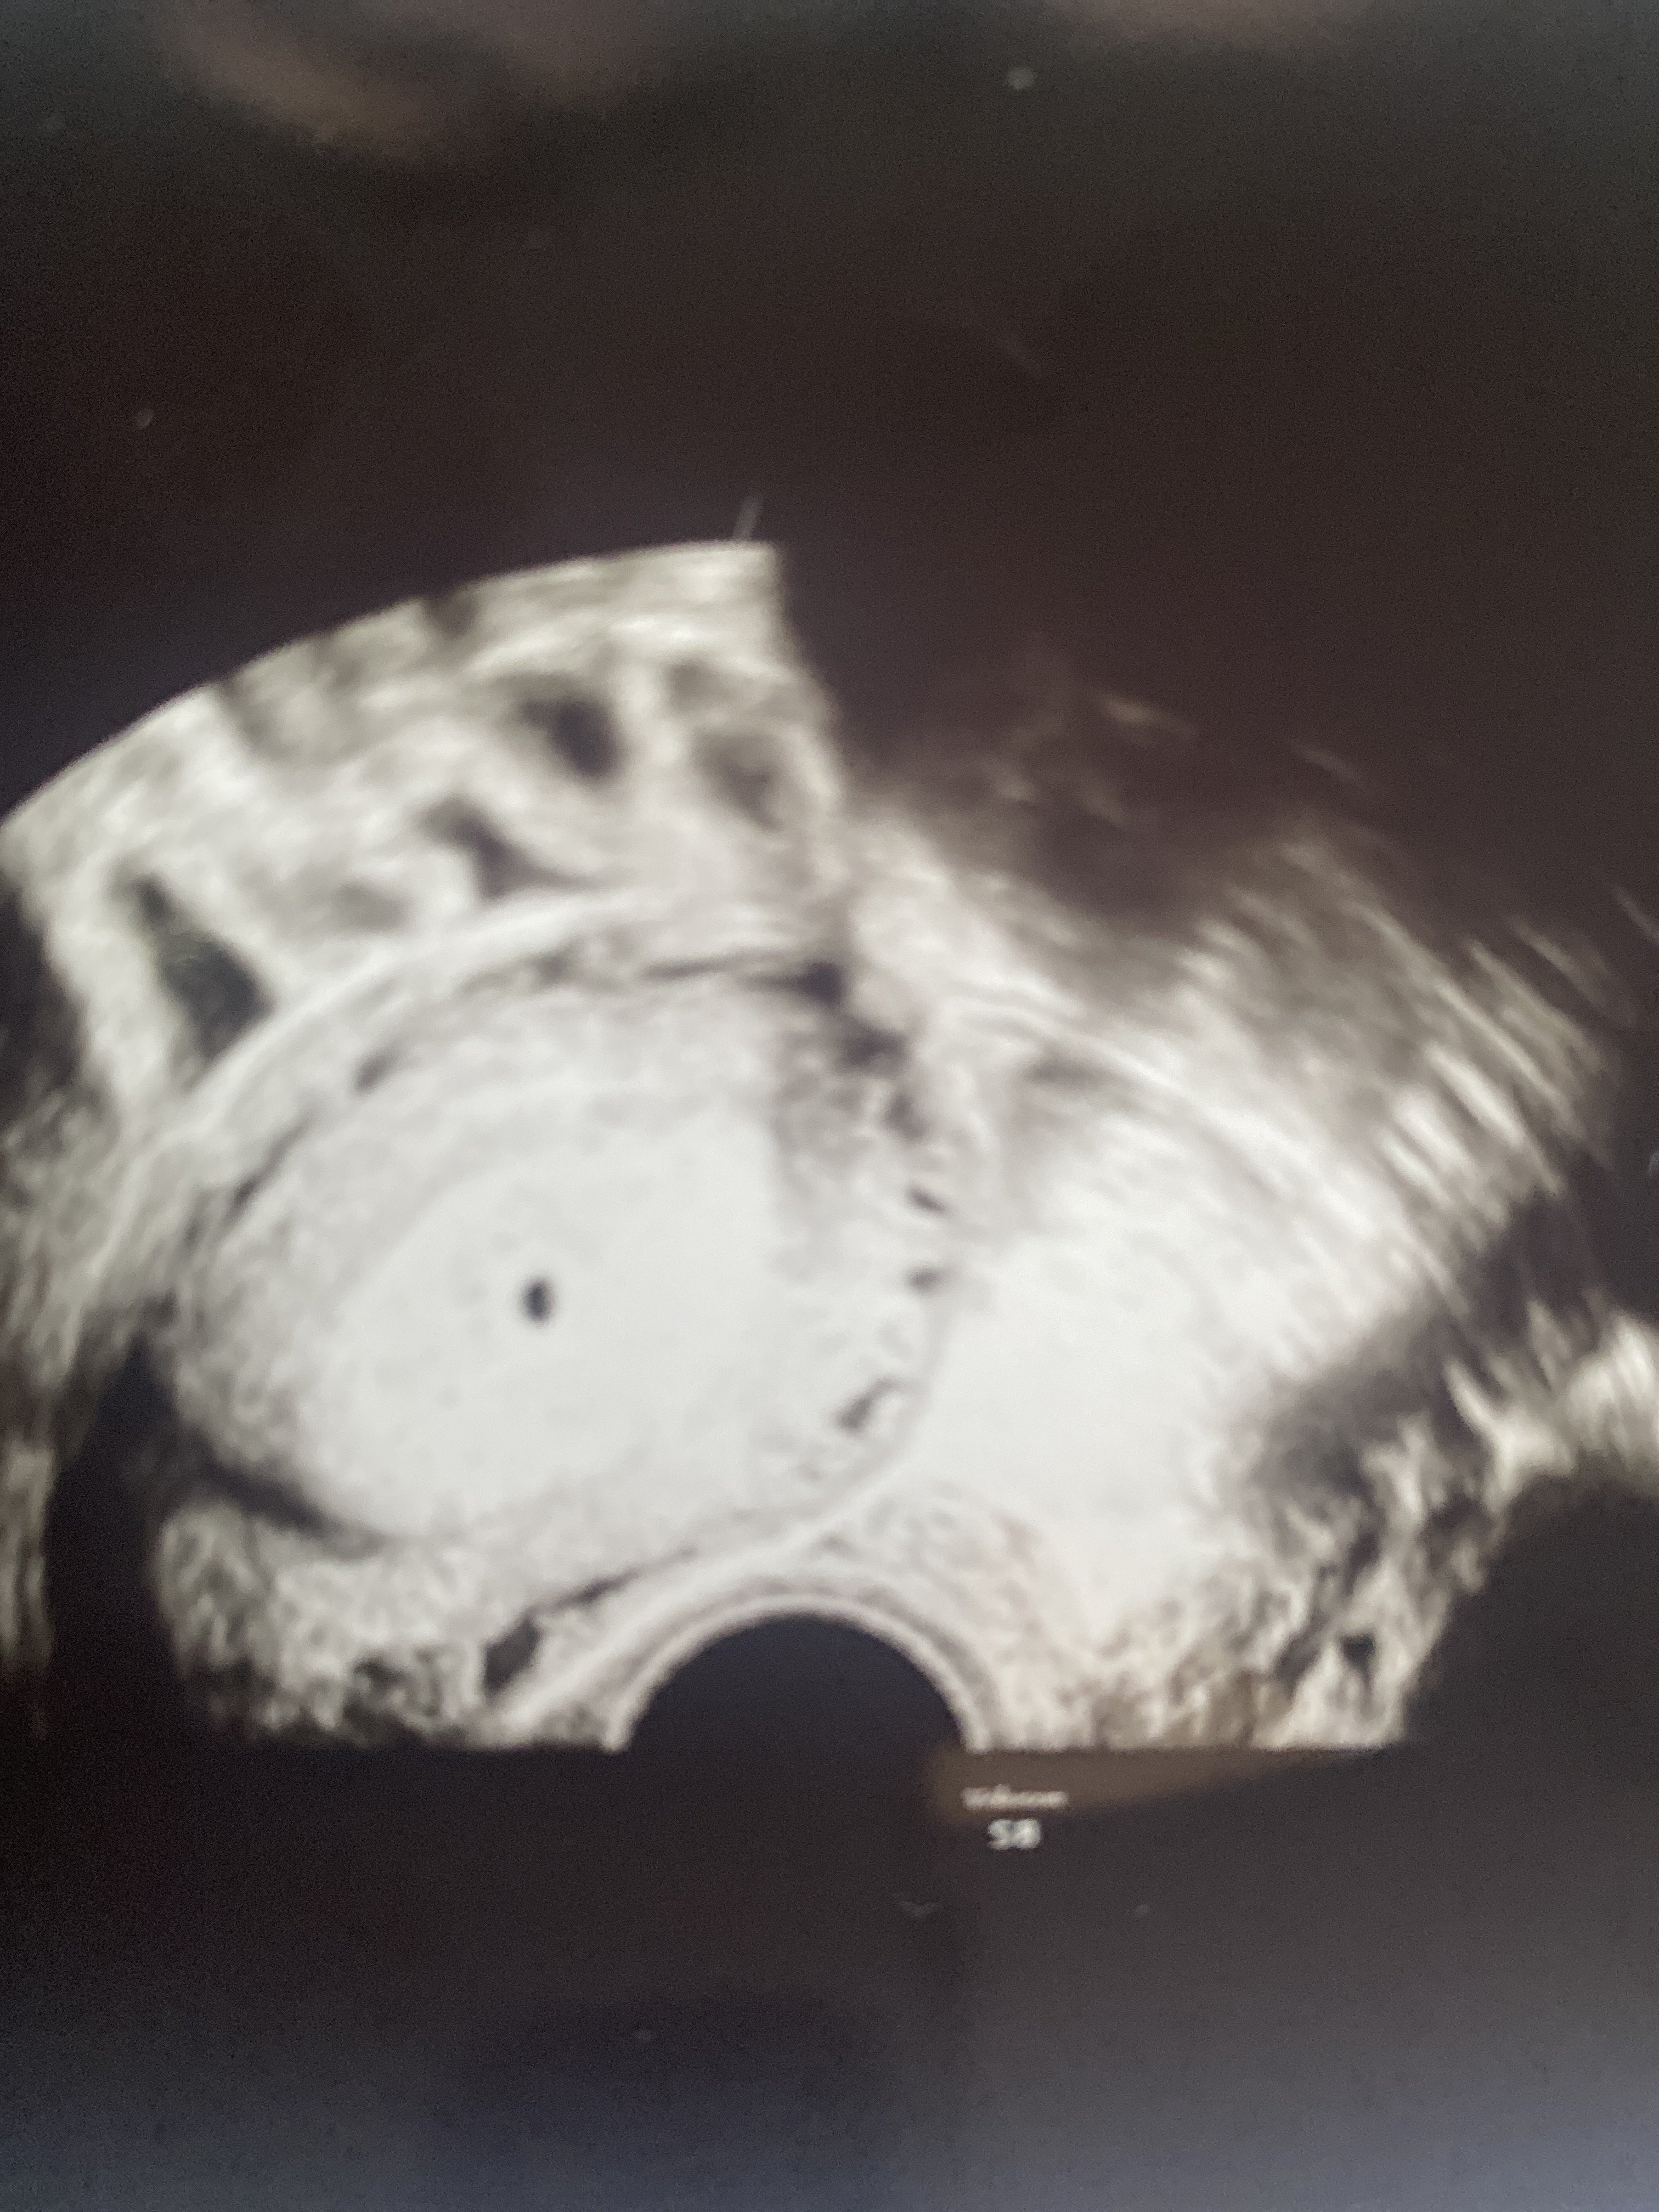

Nie mam pojęcia które zdjęcie jest czego, nie tłumaczył a ja nie pytałam, nie miałam siły na to

Załączniki

• image.jpg

image.jpg

1,9 MB · Wyświetleń: 94

1,6 MB · Wyświetleń: 96

1,7 MB · Wyświetleń: 96

Prawdopodobnie tak

Zaraz wam wstawię zdjęcia z usg i faktycznie w poprzedniej ciąży przy podobnej becie pęcherzyk był o wiele większy.

Ginekolog przekazał mi że mam coś w lewym jajniku ale nie jest w stanie mi powiedzieć czy to nie jest drugi pęcherzyk bo beta jest podejrzanie wysoka patrząc na ten co jest ulokowany w macicy i dostałam skierowanie do szpitala z ciążą pozamaciczną.

Próbowałam umówić się jeszcze na dzisiaj do mojej ginekolozki ale dzisiaj nie przyjmuje :(

Nie wiem kompletnie co robić, niby drugi lekarz mówi o pozamacicznej ale żadnej mi tego nie potwierdził. Zrobiłam znowu betę dzisiaj to porównam sobie wynik z wczorajszą i najwyżej wieczorem pojadę do szpitala lub jutro z rana…